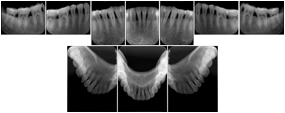

3. A dental provider wishes to capture a series of DICOM IO images for the patient’s dentition. The tooth morphology, teeth are divided into molars, premolars, canines and incisors, and a number of images for each jaw. The anatomic information was captured utilizing the triplet of schema. This standard code sequence is based on ISO 3950-2010, Dentistry - Designation system for teeth and areas of the oral cavity.

Every IO image should have anatomic information either through the primary or modifier sequence.

In most standard cases, images are oriented in structured layouts. These structured displays are useful to be shared between providers for reference purposes.

Table OO.1.1-1 shows structured display standard templates, where Viewset ID is based on the Japanese Society for Oral and Maxillofacial Radiology (JSOMR) classification provided by JIRA (Japan Medical Imaging and Radiological Systems Industries Association, www.jira-net.or.jp). Expected or typical teeth to be imaged location, region and designation codes are based on ISO 3950-2010, Dentistry - Designation system for teeth and areas of the oral cavity. For all the hanging protocols listed in OO.1.1-1, the value to use for Hanging Protocol Creator (0072,0008) is "JSOMR" and the value to use for Hanging Protocol Name (0072,0002) does not include "JSOMR" (e.g., "DL-S001A", not "JSOMR DL-S001A").